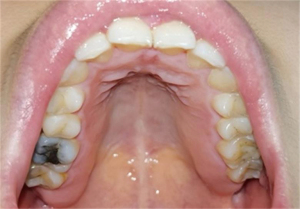

The frontal occlusal photo required the patient to expose the maximum number of teeth and gums and could be assisted by common objects. The upper teeth photo required the patient to open the mouth as much as possible and take a picture of the maxillary dentition. The patient was required to lie as flat as possible, with the maxillary occlusal surface at 90–120° to the floor after opening the mouth. The handpiece was held as low as possible, depressed or held upside down, and the full maxillary arch was photographed from the bottom up. The patient’s head was lowered slightly and their thumb and index finger were held slightly apart at the corner of the mouth while the handpiece was held diagonally upwards towards the bottom. For patients with smaller mouth openings, one photo of each of the right- and left-side teeth could also be taken. No pre-setting of lighting conditions, resolution, exposure, and other jumps in the photographic process were made for this study; all images were obtained by the device in the conventional photographic mode. In order to approximate the image effect in real-life scenarios, all images were captured using a smartphone and without professional equipment such as reflectors (Figures 1,2).

The images were collected in JPG format, with a size of 1–33 Mb. A total of 640 images were collected, and the image annotation software LabelImg (labelImg.1.8.4. November 2020. Tzu Ta Lin. https://pypi.org/project/labelImg/1.8.4/.10/12/2020) as used to annotate the caries in the image data (Figure 3).